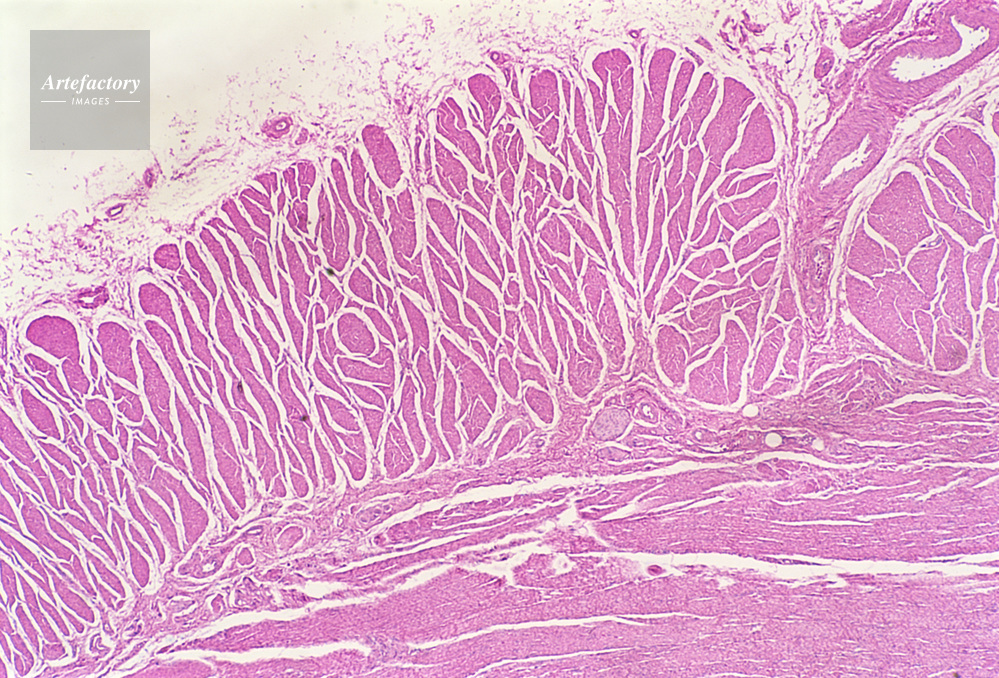

| 作品タイトル | 顕微鏡写真 | モデルリリース | なし | |

| キャプション | 食道,人間,20倍 | 制限事項 | ||